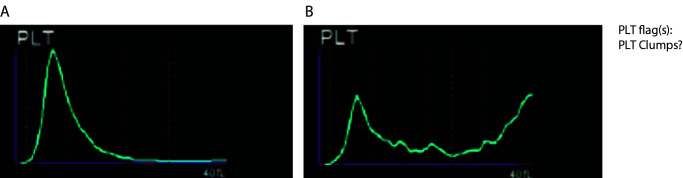

Pseudothrombocytopenia (PTCP) is defined by the occurence of spouriously low platelet count as a consequence of in vitro platelet aggregation. It is a rare and benign artifact, not associated with any specific disorder or therapy, that becomes clinically relevant when it is not timely and reliably recognized. Thus, it may result in inappropriate clinical decisions (i.e. unnecessary further testing, misdiagnoses and potential patients' mismanagement) unavoidably compromising patient safety. The most common form of PTCP is caused by ethylenediaminetetraacetic acid (EDTA). Several approaches for the management of samples with EDTA-induced PTCP have been described in the literature. However, expert recommendations are scarce. The scope of these recommendations is to assist in achieving national harmonisation in laboratory management (i.e. detecting and reporting platelet counts) of samples with EDTA-induced PTCP. These minimal recommendations were prepared by the members of the joint working group of the Croatian Chamber of Medical Biochemists and Working group for Laboratory Hematology of the Croatian Society of Medical Biochemistry and Laboratory Medicine, and might be customized according to specific conditions (i.e. personnel and equipment) of each individual laboratory. These recommendations are primarily intended to all laboratory professionals involved in the management of samples with EDTA-induced PTCP, but also to other healthcare professionals involved in collecting samples and interpreting complete blood count results.